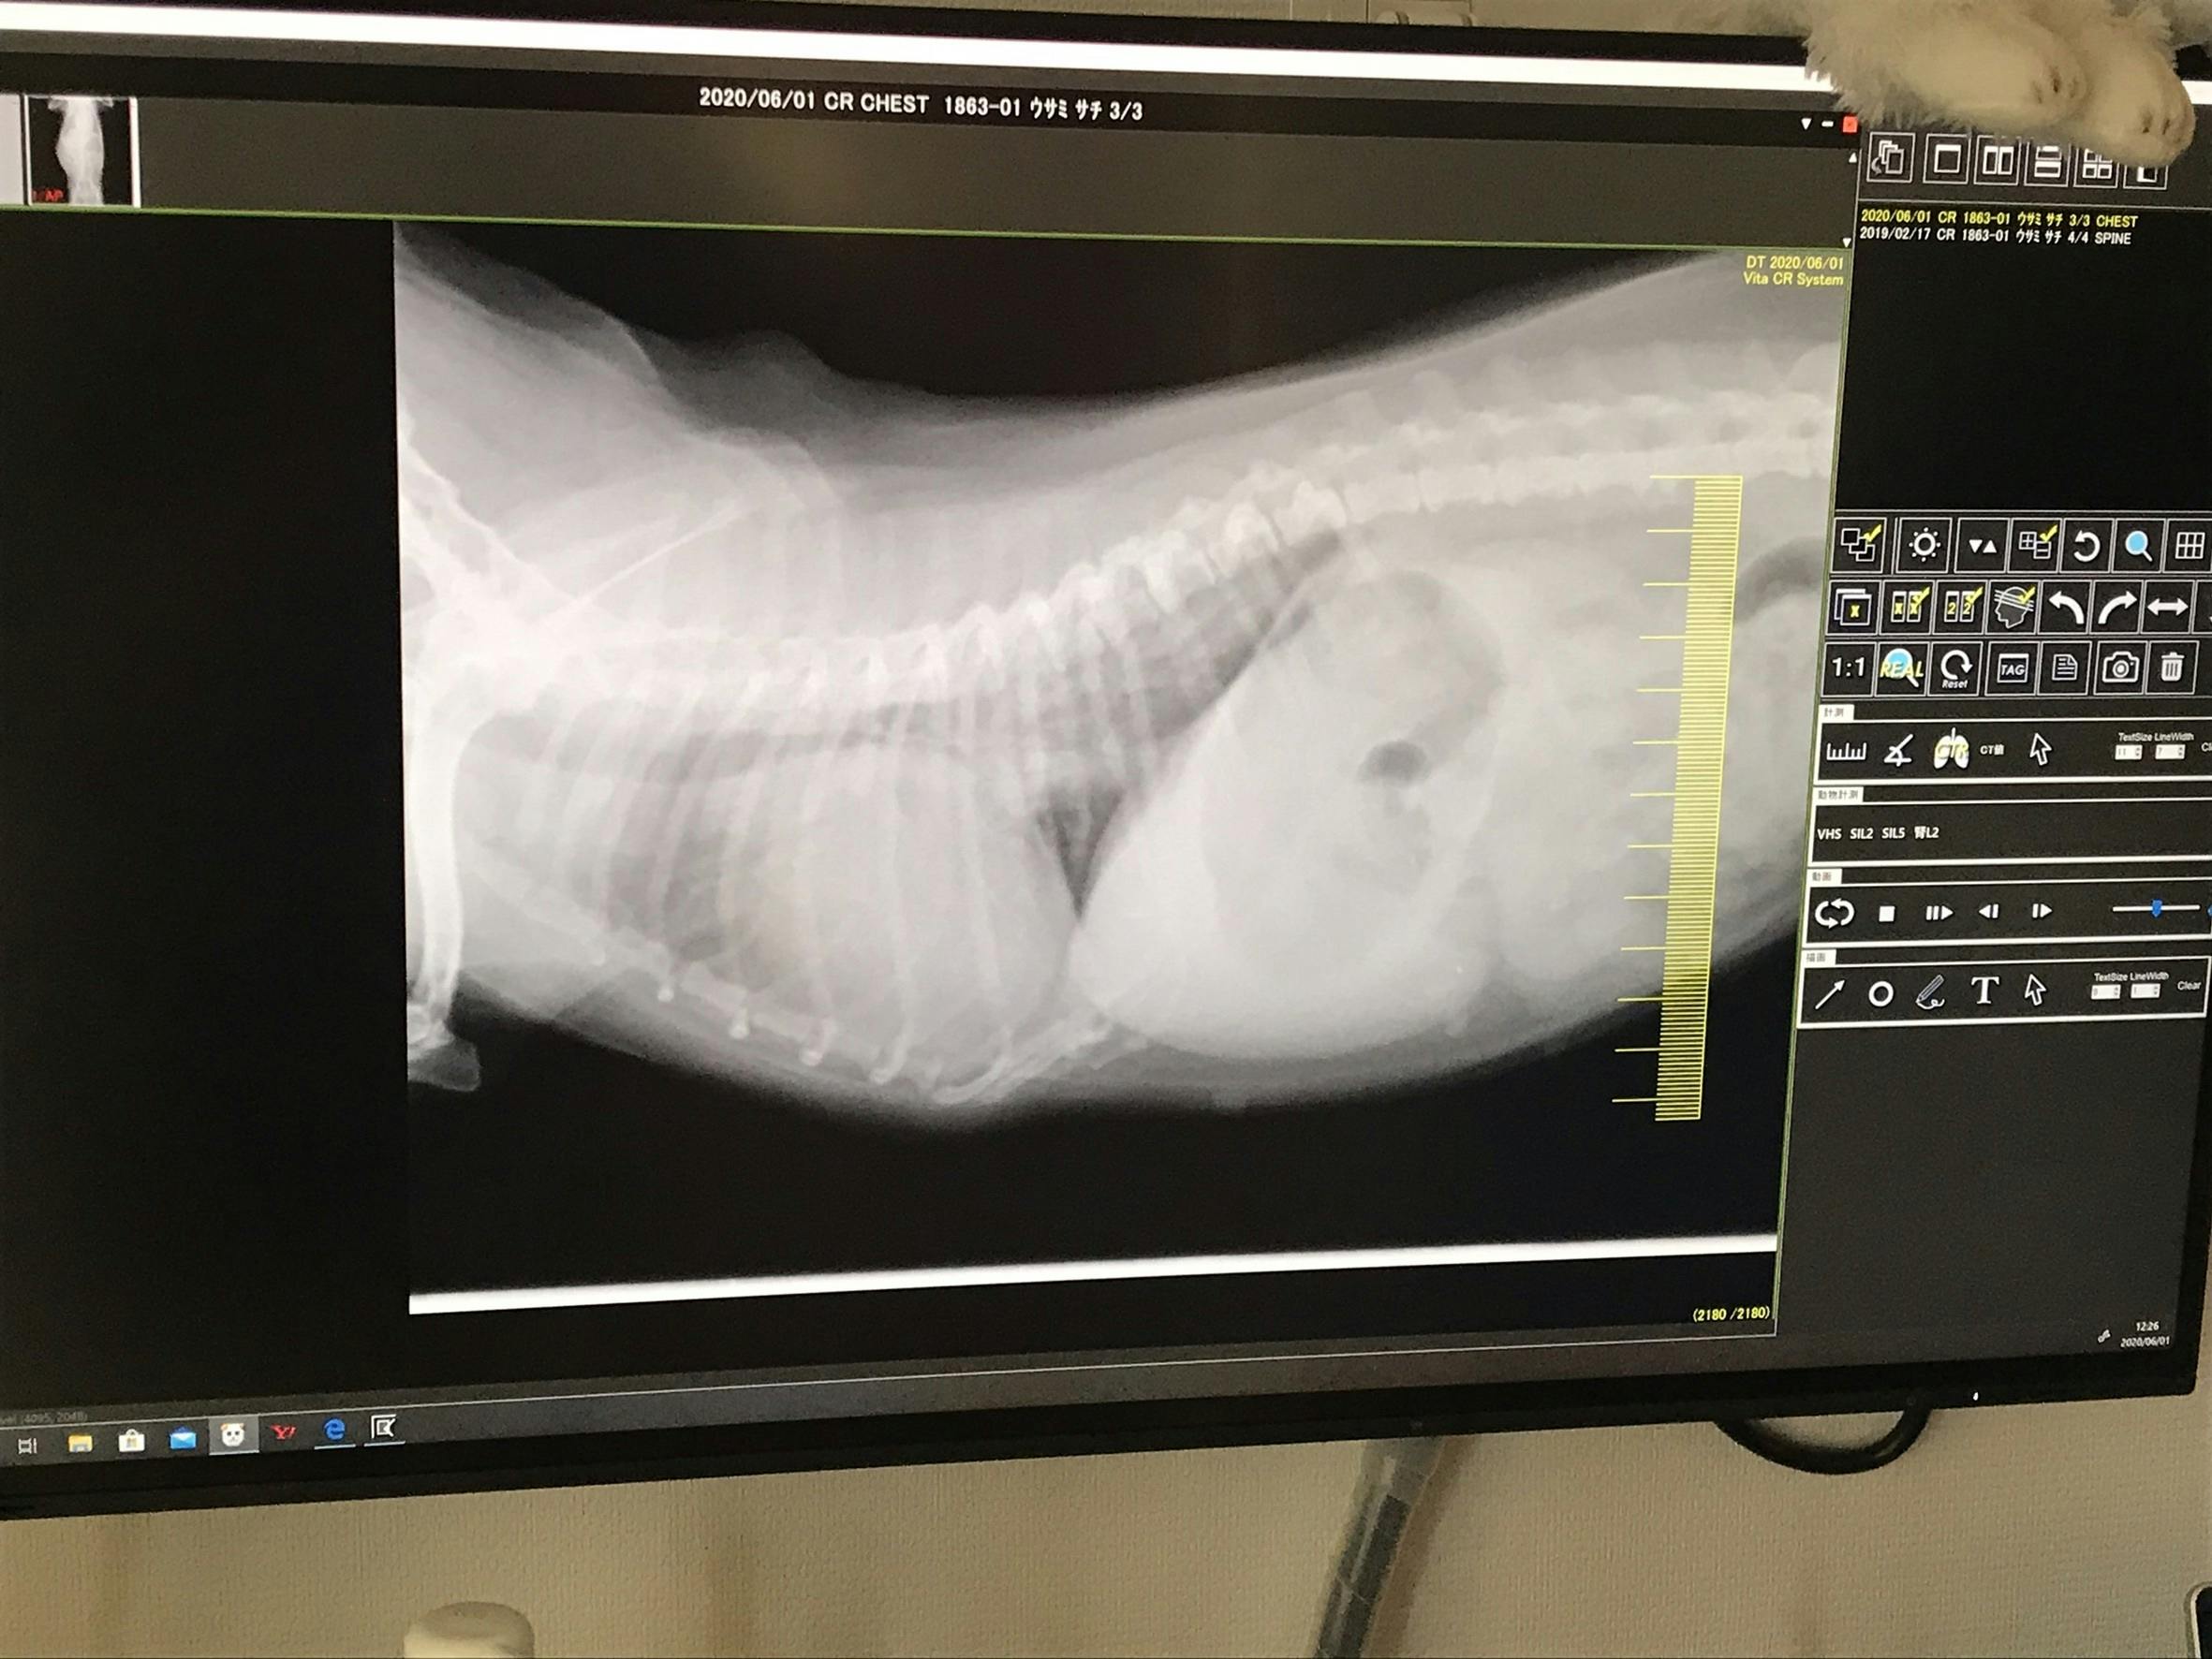

次はレントゲン写真です。心臓が肥大して肺を圧迫しております。血液が逆流するため心臓により大きい負担がかかり、心不全や肺水腫などを引き起こします。この時点で肺水腫を起こし肺に水が溜まっておりました。